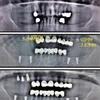

Implant tedavisi

Periimplantitis

Peri-İmplant Mukozitis